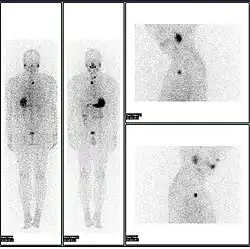

A nuclear medicine PET scan

Iodine-123 whole body scan for thyroid cancer evaluation. The study above was performed after the total thyroidectomy and TSH stimulation with thyroid hormone medication withdrawal. The study shows a small residual thyroid tissue in the neck and a mediastinum lesion, consistent with the thyroid cancer metastatic disease. The observable uptakes in the stomach and bladder are normal physiologic findings.